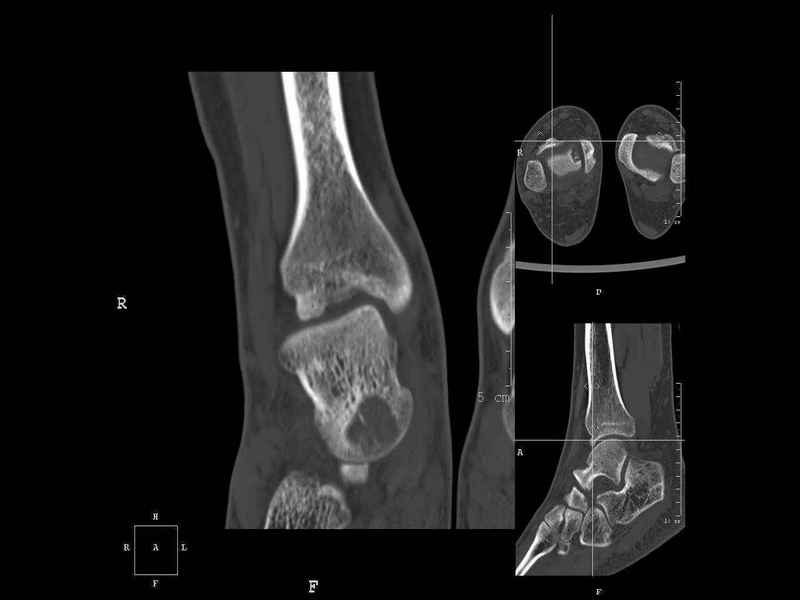

Уважаемые коллеги, обратился за помощью пациент, мужчина, 25 лет. С жалобами на болевой синдром в области голеностопного сустава и среднем отделе стопы. Травму отрицает. Со слов, болевой синдром в течении 1 года. Последние 1-1.5 мес периодически вынужден пользоваться костылями. После ограничения нагрузки боли уменьшаются.Соматически здоров. До появления болей активно занимался рукопашным боем. На СКТ картина рассекающего остеохондрита блока таранной кости, киста шейки таранной кости с признаками импрессии суставной поверхности. А также - разрастания переднего края б\берцовой кости сопровождающиеся клиникой импиджмент синдрома. Предполагаемый план лечения- удаление свободного фрагмента суставного хряща из трансмаллеолярного доступа с рассверливанием поверхности дефекта, кюретаж кисты шейки с заполнением полости биокомпозитом + дебридмент переднего отдела голеностопного сустава. Прошу высказать своё мнение, за и против, предполагаемого плана лечения. А также по возможности ответить на вопросы: 1. Есть ли необходимость в улучшении васкуляризации таранной кости (например подтаранный артродез). 2. Учитывая планируемое применение биокомпозитного цемента целесообразно ли заполнение им дефекта блока таранной кости с моделированием края суставной поверхности.

- Резекция экзостоза переднего края б.б. кости